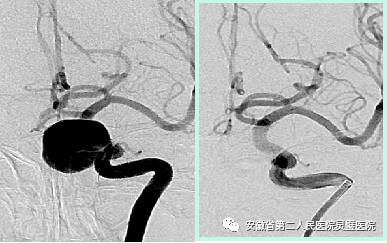

三、脑血管病的综合治疗技术

脑血管病亚专业组紧跟国际前沿,目前全面开展颅内动脉瘤、脑动静脉畸形、硬脑膜动静脉瘘等脑血管病的外科及血管内治疗,尤其对复杂颅内动脉瘤,灵活运用支架及球囊辅助、双微导管、液态栓塞剂栓塞、覆膜支架等技术,取得良好效果。开展烟雾病血管搭桥、颈内内膜剥脱术等脑血管外科手术。

前交通动脉瘤术前和术后

颈内动脉动脉瘤术前和术后